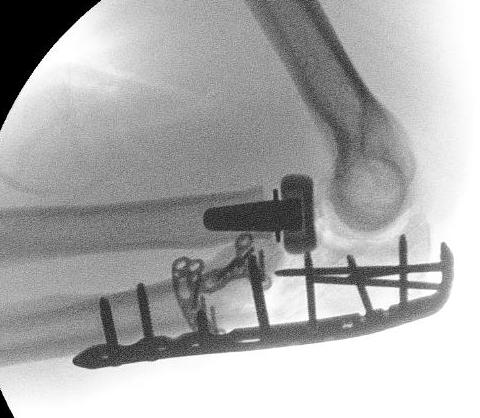

Olecranon plate + ORIF Type II coronoid process + radial head replacement

Olecranon plate with radial head replacement

Olecranon plate with radial head replacement + LCL repair

Olecranon plate + medial coronoid buttress plate + radial head replacement